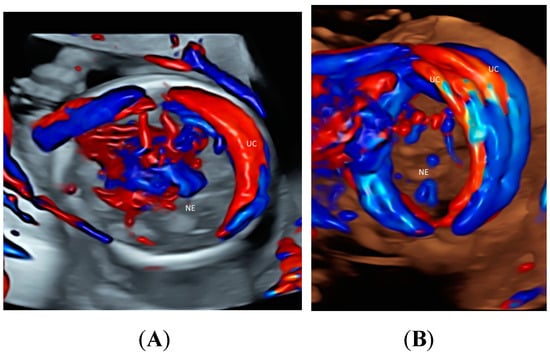

4. Umbilical Cord

| Umbilical cord | Cord vessels and insertion site (HDFI) | GBM TUI | Velamentous or marginal cord insertion, vasa previa, cord round neck, single umbilical artery, umbilical cord knot, abnormal thickening |